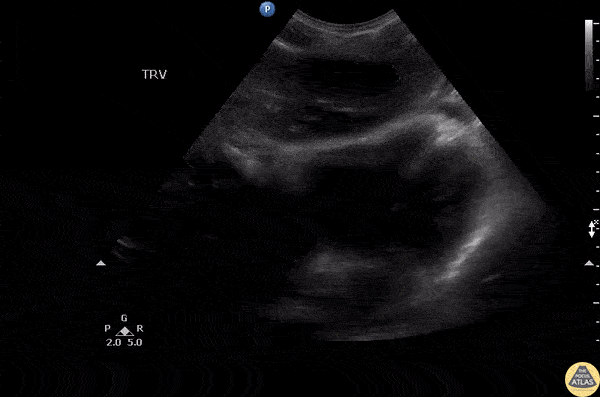

Bowel-GI - Paraesophageal Abscess

Patient presented with chest pain. A subxiphoid sweep revealed normal cardiac function with a neighboring anechoic structure confirmed as a paraesophageal abscess on CT. Image courtesy of Robert Jones DO, FACEP @RJonesSonoEM Director, Emergency Ultrasound; MetroHealth Medical Center; Professor, Case Western Reserve Medical School, Cleveland, OH View his original post here